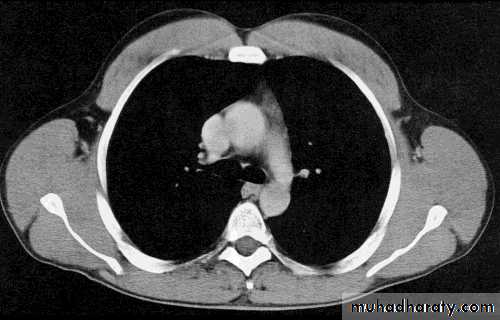

ComparisonsMRI image

CAT image

thorax

Compare bone and soft tissue density